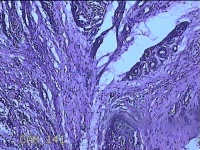

右侧手掌肉芽组织

性别

女

年龄

48岁

临床诊断

手掌开放性损伤

一般病史

右侧手掌肉芽组织增生

标本名称

大体所见

灰白暗红色带皮肤样组织1.3x0.8x0.3cm一块,切面灰白粉红色,质软。